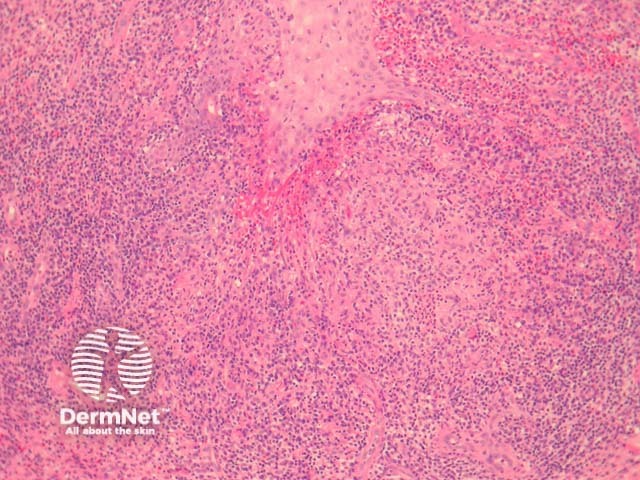

In sporotrichosis, sections show epidermal hyperplasia overlying a marked acute and chronic inflammatory response (figure 1). Higher power shows the inflammation infiltrates the overlying epidermis (figure 2). The infiltrate is polymorphous with giant cells, histiocytes, and focal neutrophilic microabscess formation (figure 3). Careful examination of multiple sections is required to identify the causative organisms (figure 4, arrows).

Figure 1